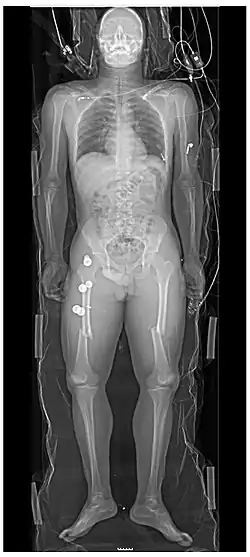

A projectional radiograph of an extremity confers an effective dose of approximately 0.001 mSv, comparable to a background radiation equivalent time of 3 hours.[16]

Certain suspected conditions require specific projections. For example, skeletal signs of rickets are seen predominantly at sites of rapid growth, including the proximal humerus, distal radius, distal femur and both the proximal and the distal tibia. Therefore, a skeletal survey for rickets can be accomplished with anteroposterior radiographs of the knees, wrists, and ankles.[20]